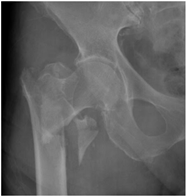

For X-ray 3, four scenarios were developed.![]() | Scenario 1: What would be your operation preference for a mobile patient aged 50–70 and with an ASA score of 1–2? Scenario 2: What would be your operation preference for a mobile patient aged 71 years or older with an ASA score of 1–2? Scenario 3: What would be your operation preference for a mobile patient aged 50–70 with an ASA score of 3–4? Scenario 4: What would be your operation preference for a mobile patient aged 71 years or older with an ASA score of 3–4? |